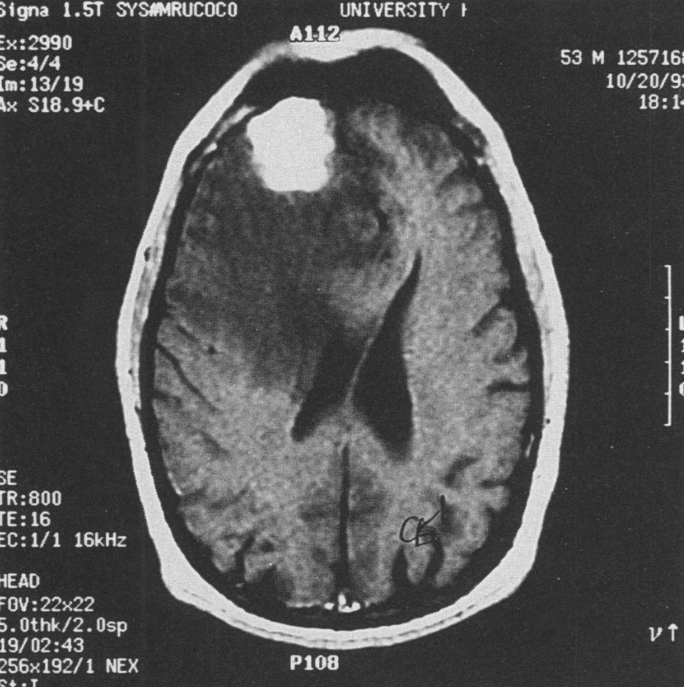

What is the most common primary malignant brain tumor in adults?

Glioblastoma

Monthly Onc Conference Dr. Donovan 12/17/2025

How may a patient present with the following imaging findings:

Personality, mood, or behavioral changes (anterior frontal lobe tumors)